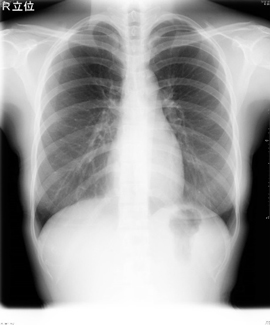

X線撮影では、骨折や結石、体の中に水がたまっている様子などが簡単かつ短時間で確認することが出来るので、放射線部門の中では一番多く撮影される検査です。